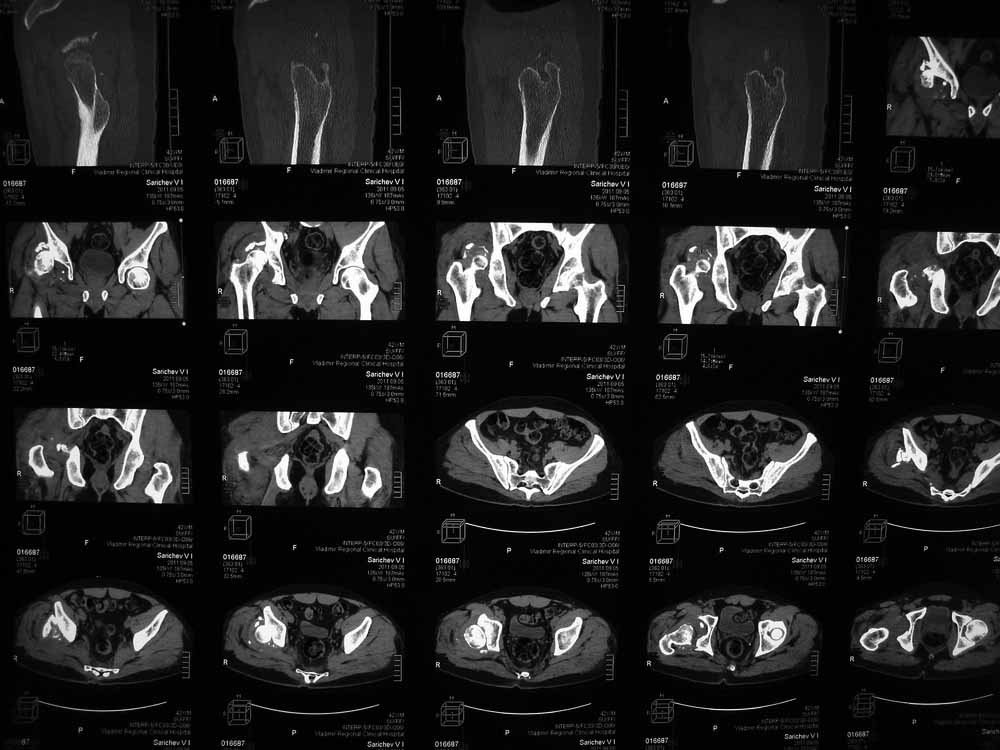

Re: Застарелый вывих бера, перелом вертлужнойвпадины, перелом головки бедра

Вот еще сканы.